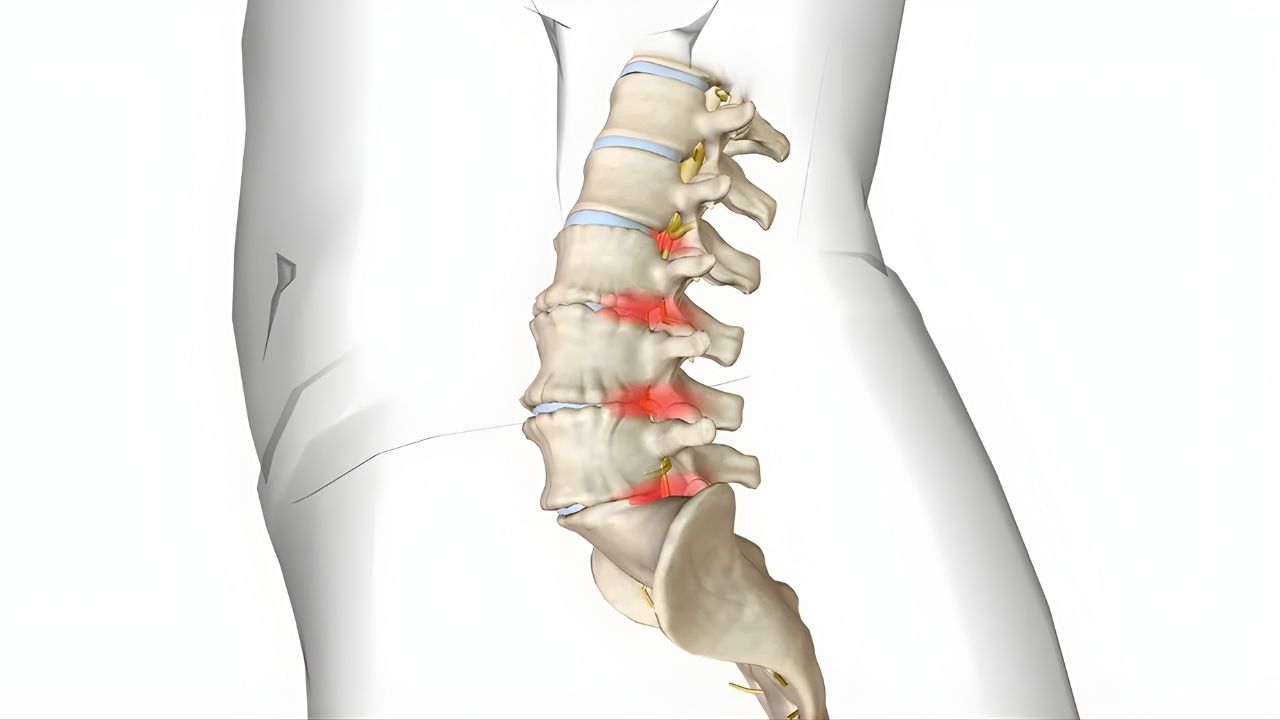

Atuação em hérnia de disco, fraturas da coluna, escoliose, estenose vertebral e processos degenerativos.